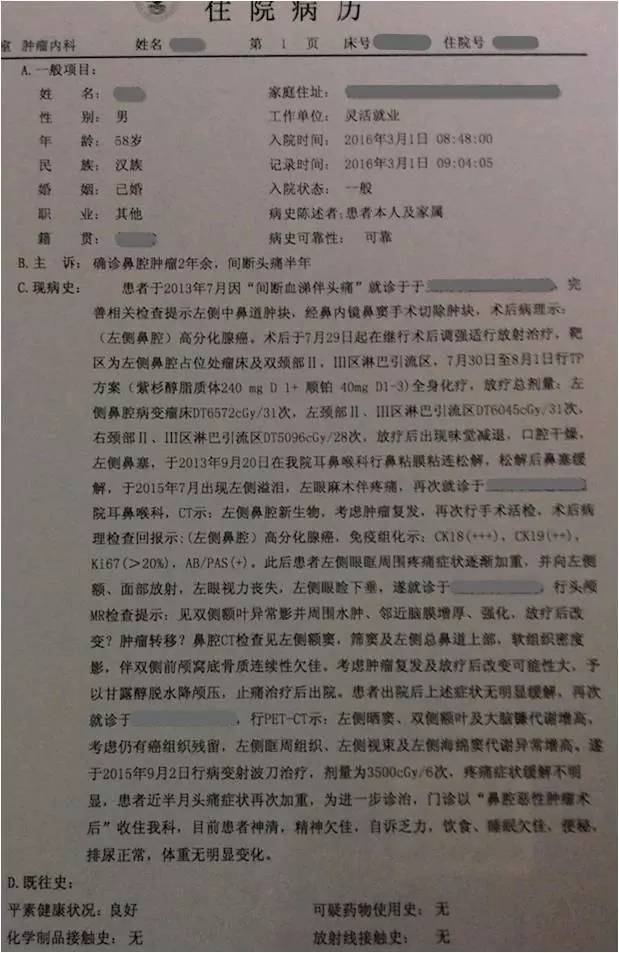

患者:男性,58岁,主因“左鼻腔高分化腺癌术后2年余”入院。

▼患者病情描述

复习病史,患者2013-7鼻内镜鼻腔肿物切除术,病理高分化腺癌,术后行同期放化疗,鼻腔局部照射65.72Gy/31f;2015-7出现前组脑神经损害症状体征,影像检查提示鼻腔及筛窦、额窦肿物,伴前颅底额叶异常强化及周围水肿,局部脑膜增厚、强化,颅底骨质不连续,考虑复发伴放射性改变;经鼻腔再次活检证实为复发;给予对症治疗症状加重,遂行PET/CT提示筛窦、双侧额叶、大脑镰、左侧眶周、海绵窦代谢增高;局部行射波刀治疗35Gy/6f,具体不详;疗后症状无明显缓解。首先双侧额叶改变MRI不能区别放射性脑坏死和肿瘤复发,可考虑进一步MRS、PWI、DWI成像提供更多的信息鉴别两者;倾向于肿瘤复发可能性大,原因如下:病变范围可能远远超出照射野;距放疗时间较短,文献报道一般放射性脑坏死中位发生时间约6年;颅底骨质破坏伴代谢增高,且与鼻腔、筛窦、左眶、海绵窦代谢一致。当然也不排除同时合并放射性损害,毕竟同时行化疗,可能较单纯放疗反应重。关于是否再行放疗改善症状,取决于前2次放疗的评价,看危及器官尤其是脑干、健侧视神经是否还能耐受;可使用卡马西平0.1、Tid,可能减轻神经痛症状;对症支持治疗方面适当应用激素、甘露醇等减轻脑水肿;也可考虑联合贝伐单抗;后续肿瘤治疗以化疗为主,请Z主任斟酌方案。